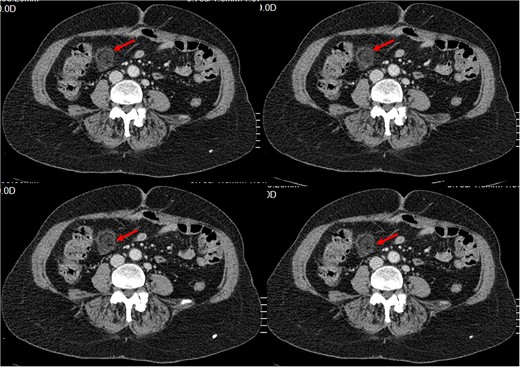

History of Present Illness: The patient reported a sudden onset of sharp pain in the right lower quadrant of the abdomen with no other symptoms. Physical examination revealed tenderness in the same area. Blood work showed an elevated white blood cell count of 13.10 × 1000/𝜇l (4, 8–10) with neutrophilia (87.3%). And C- reactive protein at 45. A CT scan was performed, which showed a typical ‘dot sign’ (Fig. 1), confirming the diagnosis of EA.

Small intra-peritoneal ovoid fatty mass, well limited by a thin border «Ring Sign/ central dot sign», enhanced after contrast, surrounded by inflammatory changes.

Outcome: The patient’s pain disappeared and tenderness in the right lower quadrant resolved. Follow-up imaging showed resolution of the ‘dot sign’.

In CT imaging, normal epiploic appendages are not easily noticeable. However, they can become visible when they become inflamed or surrounded by ascites. The most common CT feature in acute EA is an oval lesion less than 5 cm in diameter (typical diameter range, 1.5–3.5 cm) that has attenuation equivalent to that of fat, that abuts the anterior colonic wall, and that is surrounded by inflammatory changes, which has recently been referred to in recent studies as the central dot sign [11, 12].